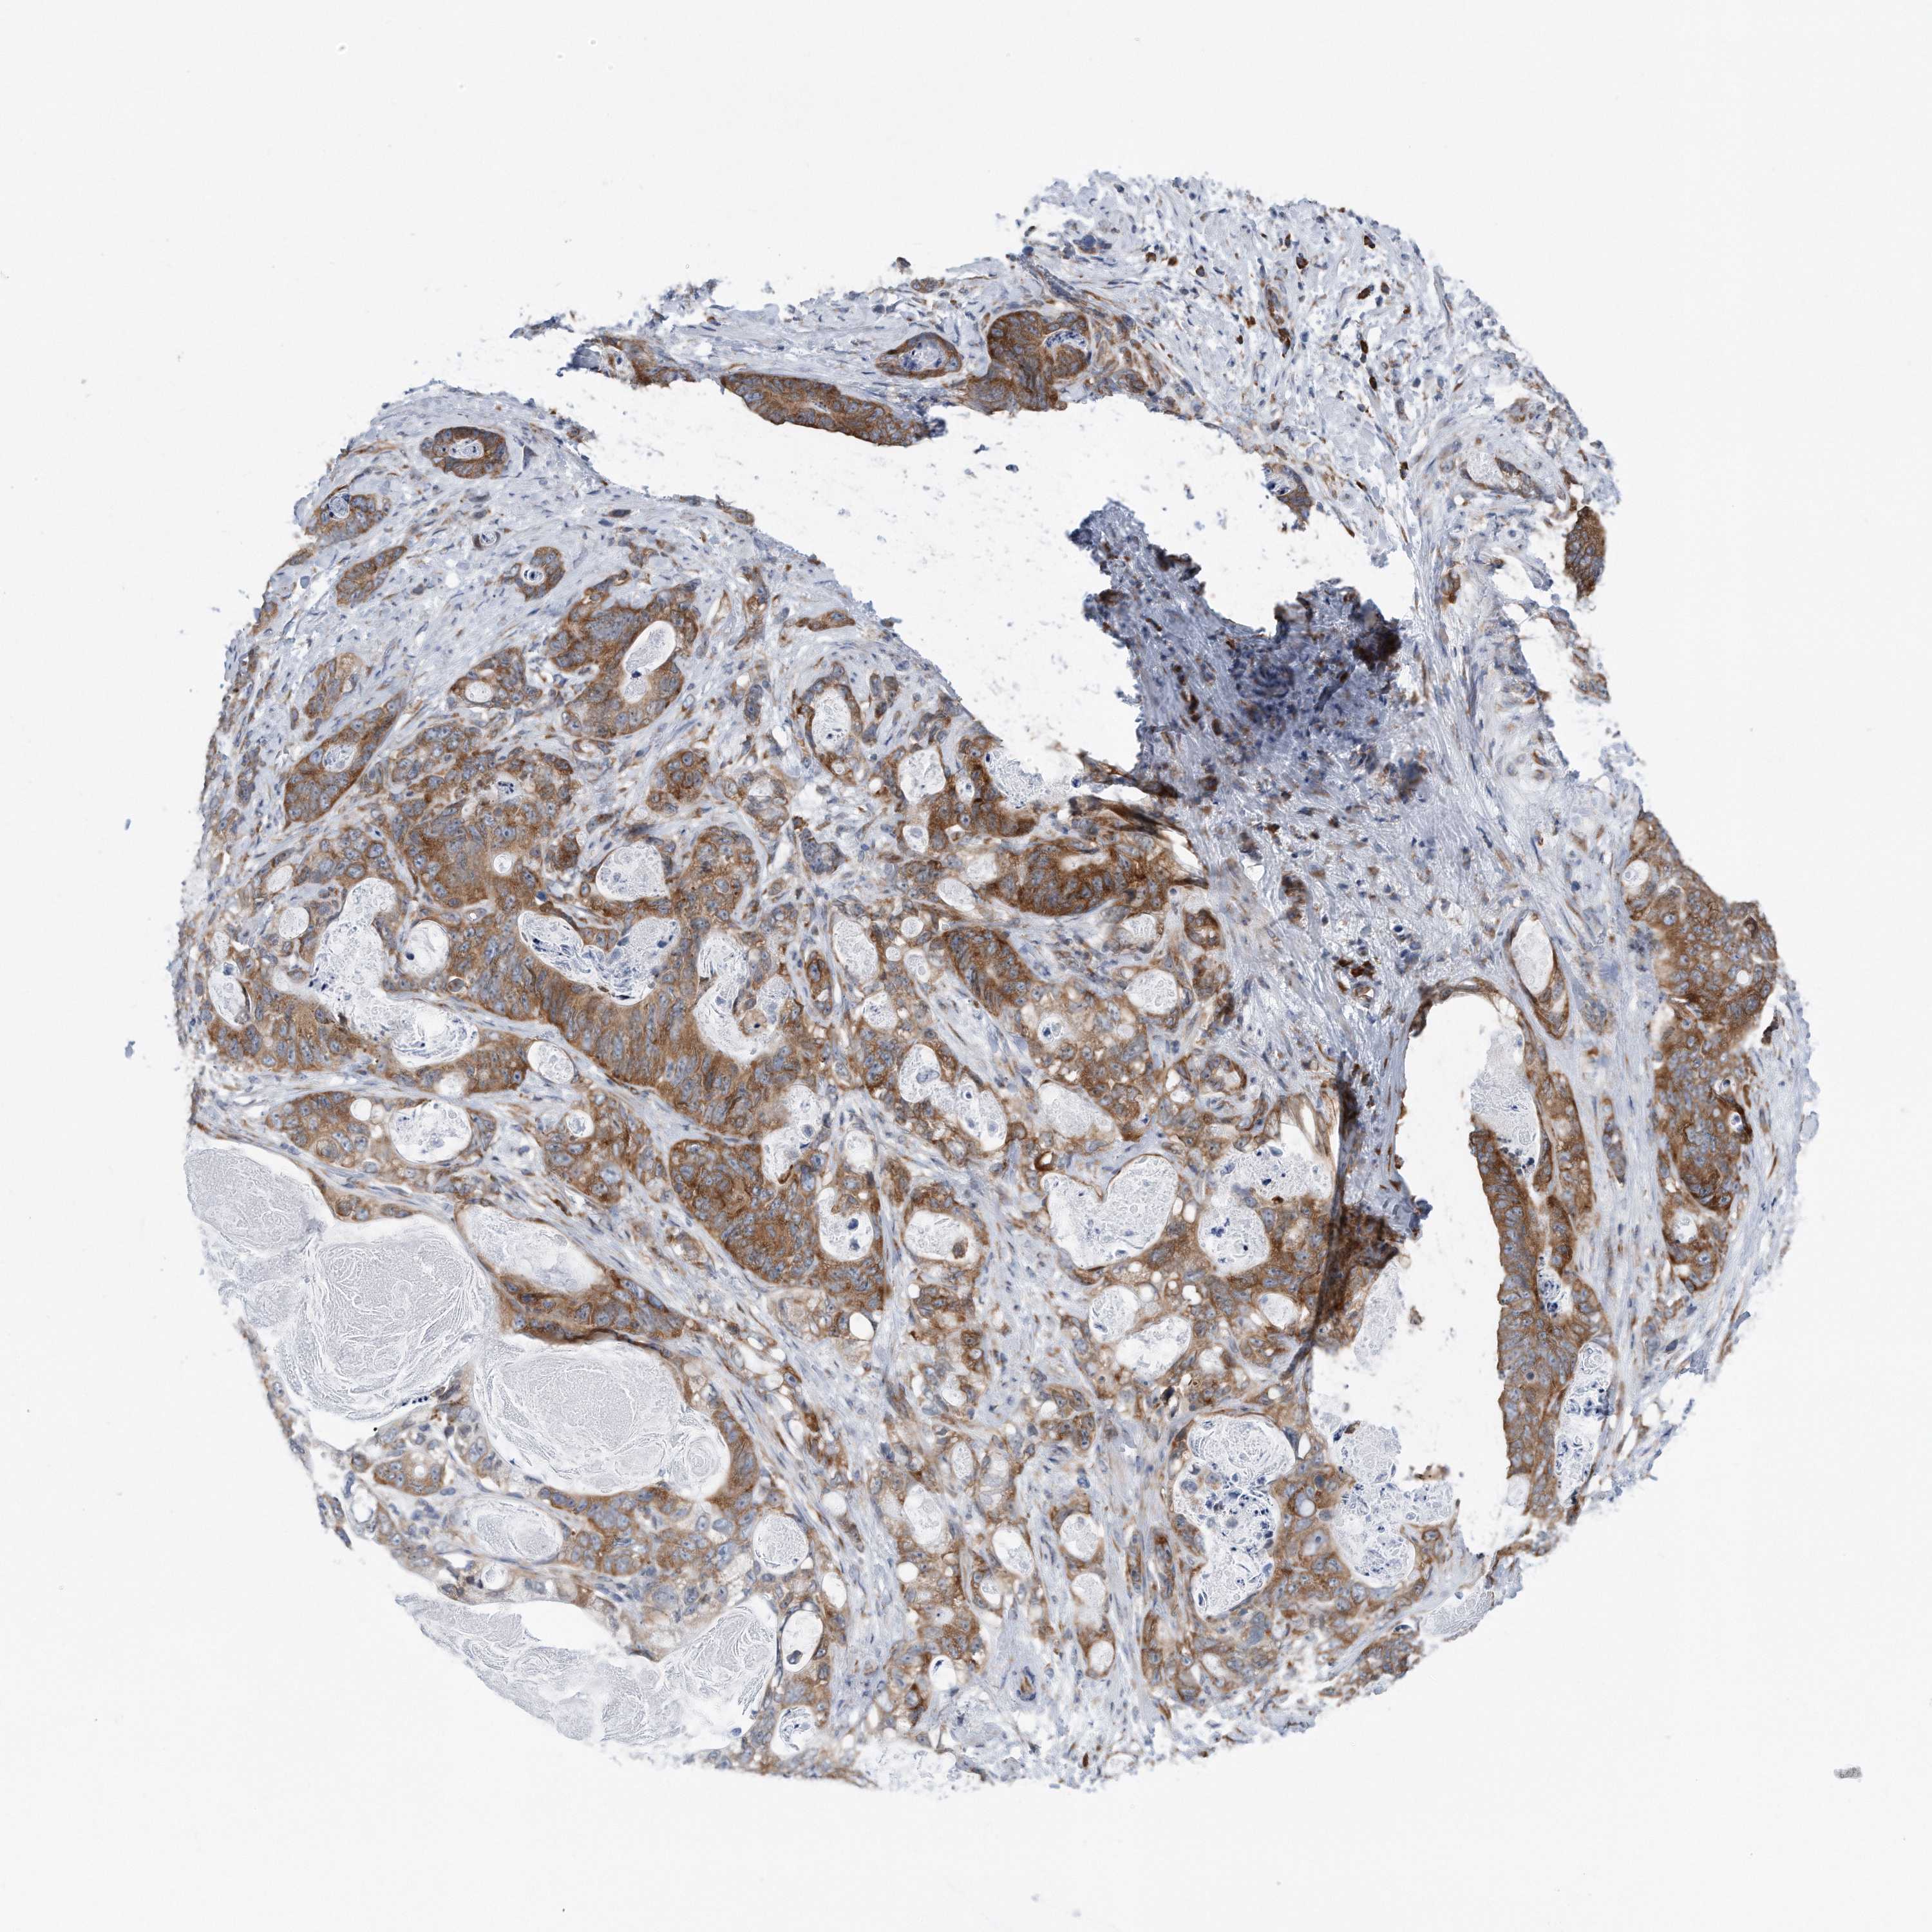

STOMACH CANCER - Protein expressioni

A mouse-over function shows sample information and annotation data. Click on an image to view it in a full screen mode. Samples can be filtered based on level of antibody staining by selecting one or several of the following categories: high, medium, low and not detected. The assay and annotation is described here.

Note that samples used for immunohistochemistry by the Human Protein Atlas do not correspond to samples in the TCGA dataset.

Antibody stainingi

Antibody staining in the annotated cell types in the current human tissue is reported as not detected, low, medium, or high, based on conventional immunohistochemistry profiling in selected tissues. This score is based on the combination of the staining intensity and fraction of stained cells.

Each image is clickable and will lead to virtual microscopy that enables deeper exploration of all samples and also displays staining intensity scores, fraction scores and subcellular localization as well as patient and tissue information for each sample.

Antibody HPA030449

Antibody CAB037301

Staining

High

Medium

Low

Not detected

Intensity

Strong

Moderate

Weak

Negative

Quantity

>75%

75%-25%

<25%

None

Location

Nuclear

Cytoplasmic/membranous

Cytoplasmic/membranous,nuclear

Adenocarcinoma, NOS